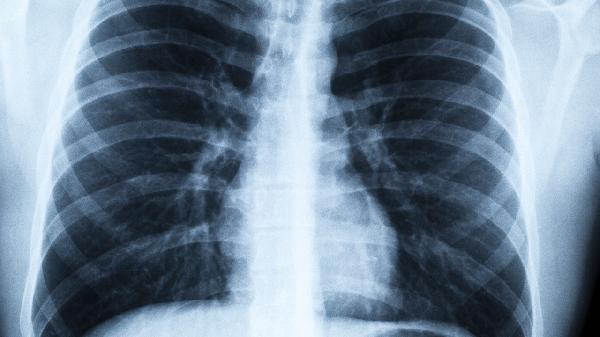

肺就像身体的"空气净化器",24小时不停歇地工作。当这个精密仪器出现问题时,其实会发出很多求.救信号,只是我们常常忽略了这些身体密码。别等咳嗽不止才想起关心肺部健康,这几个预警信号比天气预报还准!